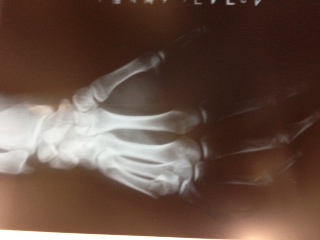

こんにちは、神戸営業所の今川です。 先日、右手(利き手)薬指、骨折!しました。これが…ザ、骨折…。